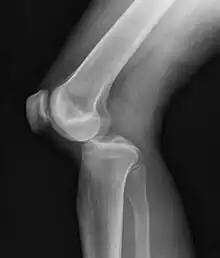

Plain lateral X-ray of the left knee showing a posterior knee dislocation[1]